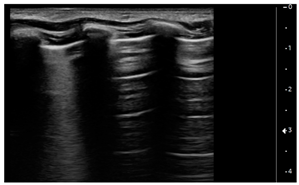

We used the following definitions to characterize the LUS patterns [15]:

- A-lines: normal appearance of horizontal, equidistant, parallel artefacts originating at regular intervals from the pleural line (visceral and parietal pleura)

- B-lines: laser-like signals arising from the hyper-echoic pleural line, extending to the bottom of the screen without fading and moving synchronously with respiration

- Subpleural consolidation: Small, triangular, or oval shaped, echo-poor region adjacent to the pleura without a tissue-like pattern (AB)

- Lobar consolidation: Large, hypoechogenic region adjacent to the pleura with a tissue-like pattern (AB) and an irregular pleural border

- Pleural effusion: Anechoic or hypoechoic collection external to lung parenchyma, typically in a dependent lung region with or without respiratory movement of the lung within the effusion (flapping lung)

Using the mentioned LUS semeiotics, lung aeration and lung pattern were classified following a 5 point score:

- Normal lung sliding, regular pleural line, and A lines

- Vertical artifacts, pleural line indented with several B-lines per field in the posterior regions

- Vertical artifacts, pleural line indented with several B-lines per field in all regions

- Broken pleural line with subpleural consolidations < 1 cm

- Consolidations > 1 cm with or without pleural effusion (Table 1).